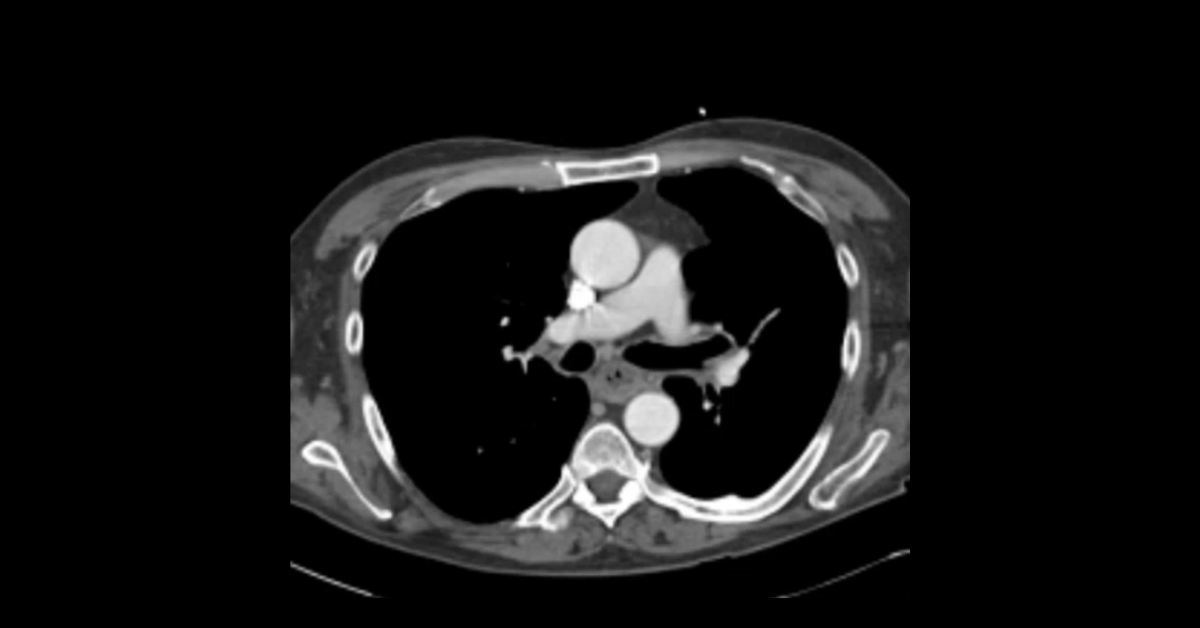

Presented by Ashish Khandelwal, MBBS, MD at Practical Radiology 2025. This talk will allow you to understand appropriate use of multimodal imaging in pregnant patient and know the imaging features of commonly encountered acute abdominopelvic conditions during pregnancy.